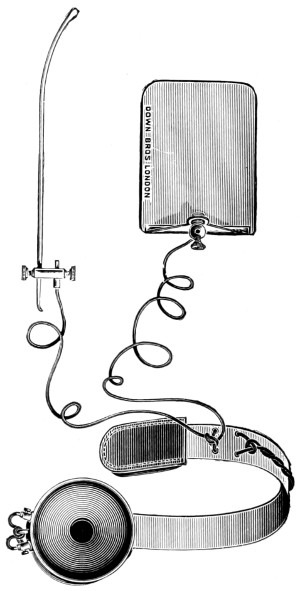

| 89 A and B. Sheen’s bullet probe, forceps, and telephone bullet-detector[xi] | 302, 303 |

| 53. A basic fracture with laceration of both carotid arteries | 148 |